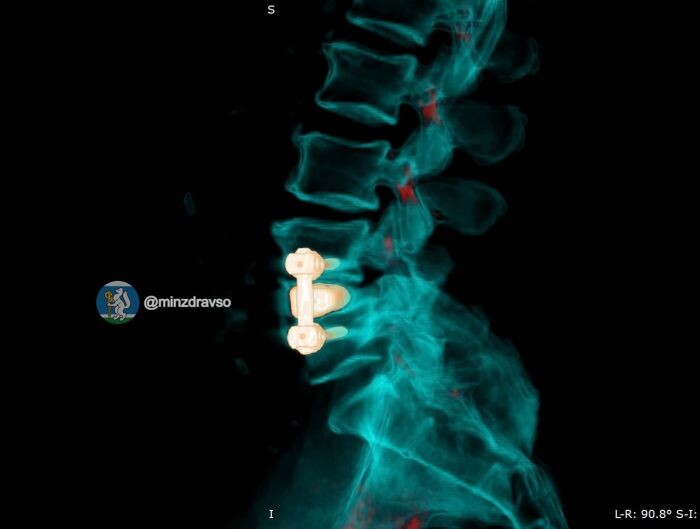

Нейрохирурги Свердловского областного госпиталя для ветеранов войн провели сложную двухэтапную операцию на позвоночнике 52-летнему водителю службы скорой помощи. Пациент много лет работал водителем, доставляя тяжёлых больных в больницы Екатеринбурга, а в этом году сам оказался на операционном столе.

Проблемы у мужчины начались после давней операции на поясничном отделе позвоночника. Организм стал отторгать установленную ранее металлическую конструкцию, развилась периимплантная инфекция, состояние пациента резко ухудшалось.

Сначала нейрохирурги удалили инфицированную конструкцию и выполнили санацию очага воспаления. Далее пациент прошёл курс интенсивной антибактериальной терапии и предоперационной подготовки. После мужчине установили титановый 3D-имплант, изготовленный по его индивидуальным анатомическим параметрам, а фиксацию позвоночника выполнили российскими спонгиозными винтами.

В первые сутки после второй операции у пациента полностью прошли все боли. Мужчина сумел встать на ноги и начал ходить без помощи. Сейчас он проходит реабилитацию и готовится к выписке.